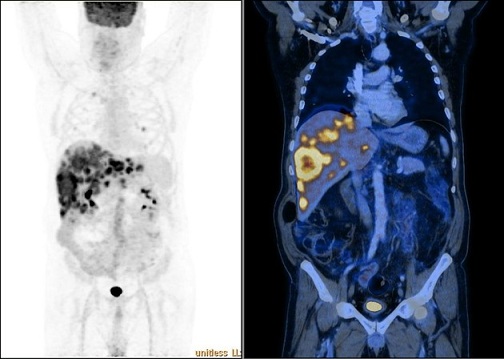

Image radiologique du PET / CT

d'une metastase de cancer du colon . |